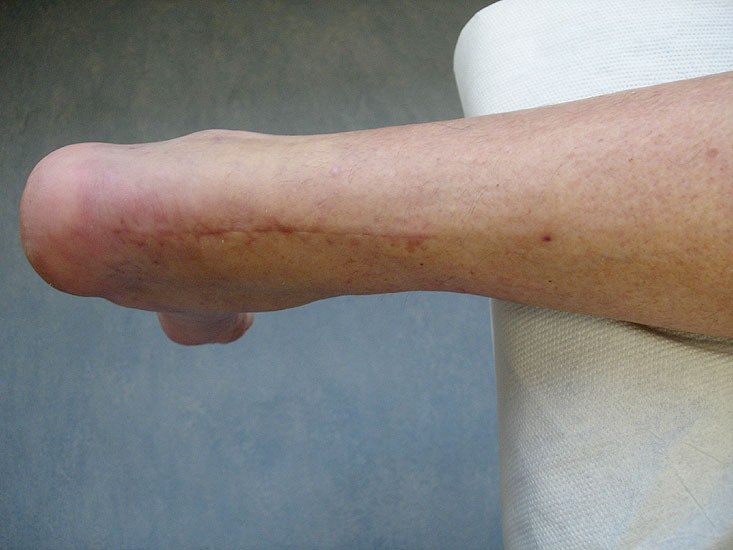

Langstreckige Defekte der Achillessehne stellen den Operateur oft vor große Schwierigkeiten, unabhängig davon, ob der Defekt durch mehrfache Rupturen, schwere degenerative Veränderungen des Sehnenmaterials oder durch eine Infektion nach Achillessehnennaht entstanden ist 1. Neben der Transposition des M. peronaeus brevis, die von Hepp und Blauth 1978 vorgestellt wurde 2, der immer eine Schwächung der Pronation und der aktiven lateralen Stabilisierung nach sich zieht, wurde die Transposition der Sehne des M. flexor hallucis longus zur Augmentation der Achillessehne erstmalig von Wapner 1993 3 beschrieben. Aufgrund der technisch einfachen Durchführbarkeit und den zuverlässig guten Ergebnissen hat sich dieses Verfahren gegenüber der Transposition des M. peronaeus brevis weitgehend durchgesetzt und wird heute von der Mehrzahl der Operateure eingesetzt.

Langstreckige degenerative Ruptur der Achillessehne.

• Langstreckige Defekte der Achillessehnen von >5 cm (Typ Myerson III) 6.

• Schwere, langstreckige degenerative Veränderungen der Achillessehne mit Ruptur (Abb. 1).